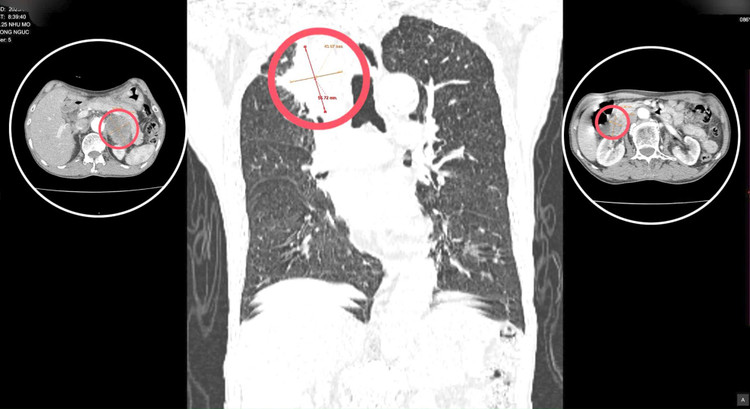

| Phát hiện 3 khối u sau 30 năm không khám sức khỏe. Ảnh TTYT huyện Thanh Ba |

Sau khi thăm khám và làm các cận lâm sàng cần thiết người bệnh được phát hiện có khối u phế quản phổi phải, theo dõi u ác của phế quản phổi và khối u tuyến thượng thận 2 bên. Người bệnh được bác sĩ tư vấn và chuyển tuyến điều trị thích hợp.